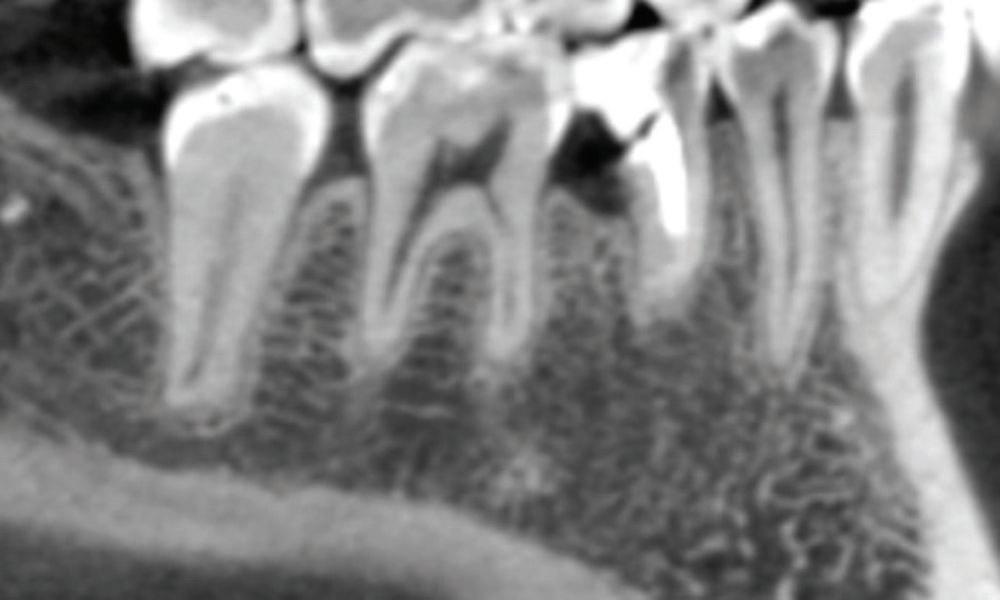

Clear radiographs are essential to accurate diagnosis and are a special test that dentists per form regularly many times throughout the day. Following the ALARA principle, we want to ensure we take a minimal number of radio graphs to ensure low radiation dosage so to repeat radiographs due to operator error should be avoided. The use of film holders allow the clinician to visualise how the radiographs should be taken to optimise the clarity of the image and ensure the diagnostic value of the image. Hawe Solutions x-ray film holders...

Figure 1: Radiographic Image of implants do not demonstrate bone loss due to the bisecting angle of the radiograph taken.

Figure 2: Radiographic image in a paralleling technique of implants dem onstrate moderate peri-implantitis with bone loss that will necessitate treatment.

• Allow exact posi tioning of the film or phosphor plate relative to the tooth - no bending and thus no distortion;

• Require no guesswork - exclusive, automatic reliance on the extraoral aiming and centring device;

• Deliver semi-reproducible images (quasi standardisation)the use of film holders allows some sense of reproducibility for assessment over time; and

• Produce optimally clear radiographs.